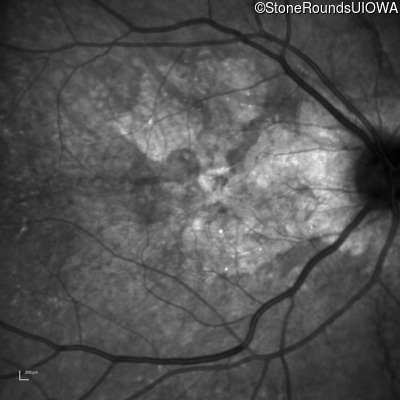

Infrared Fundus Photograph - Right - 20/25 +1

Exemplar